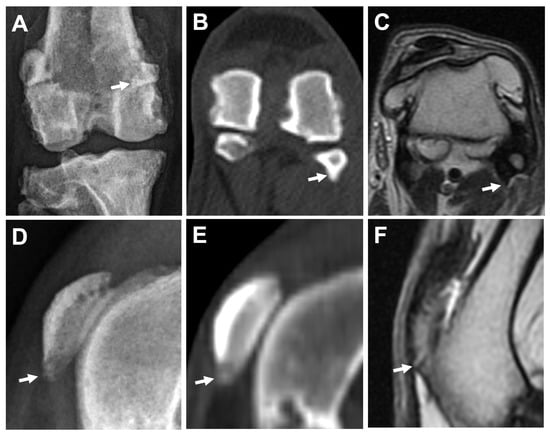

3.2.1. Osteophytes/Enthesophytes

3.2.4. Subchondral Bone Lesions

3.2.5. Meniscal and Cartilage Lesions